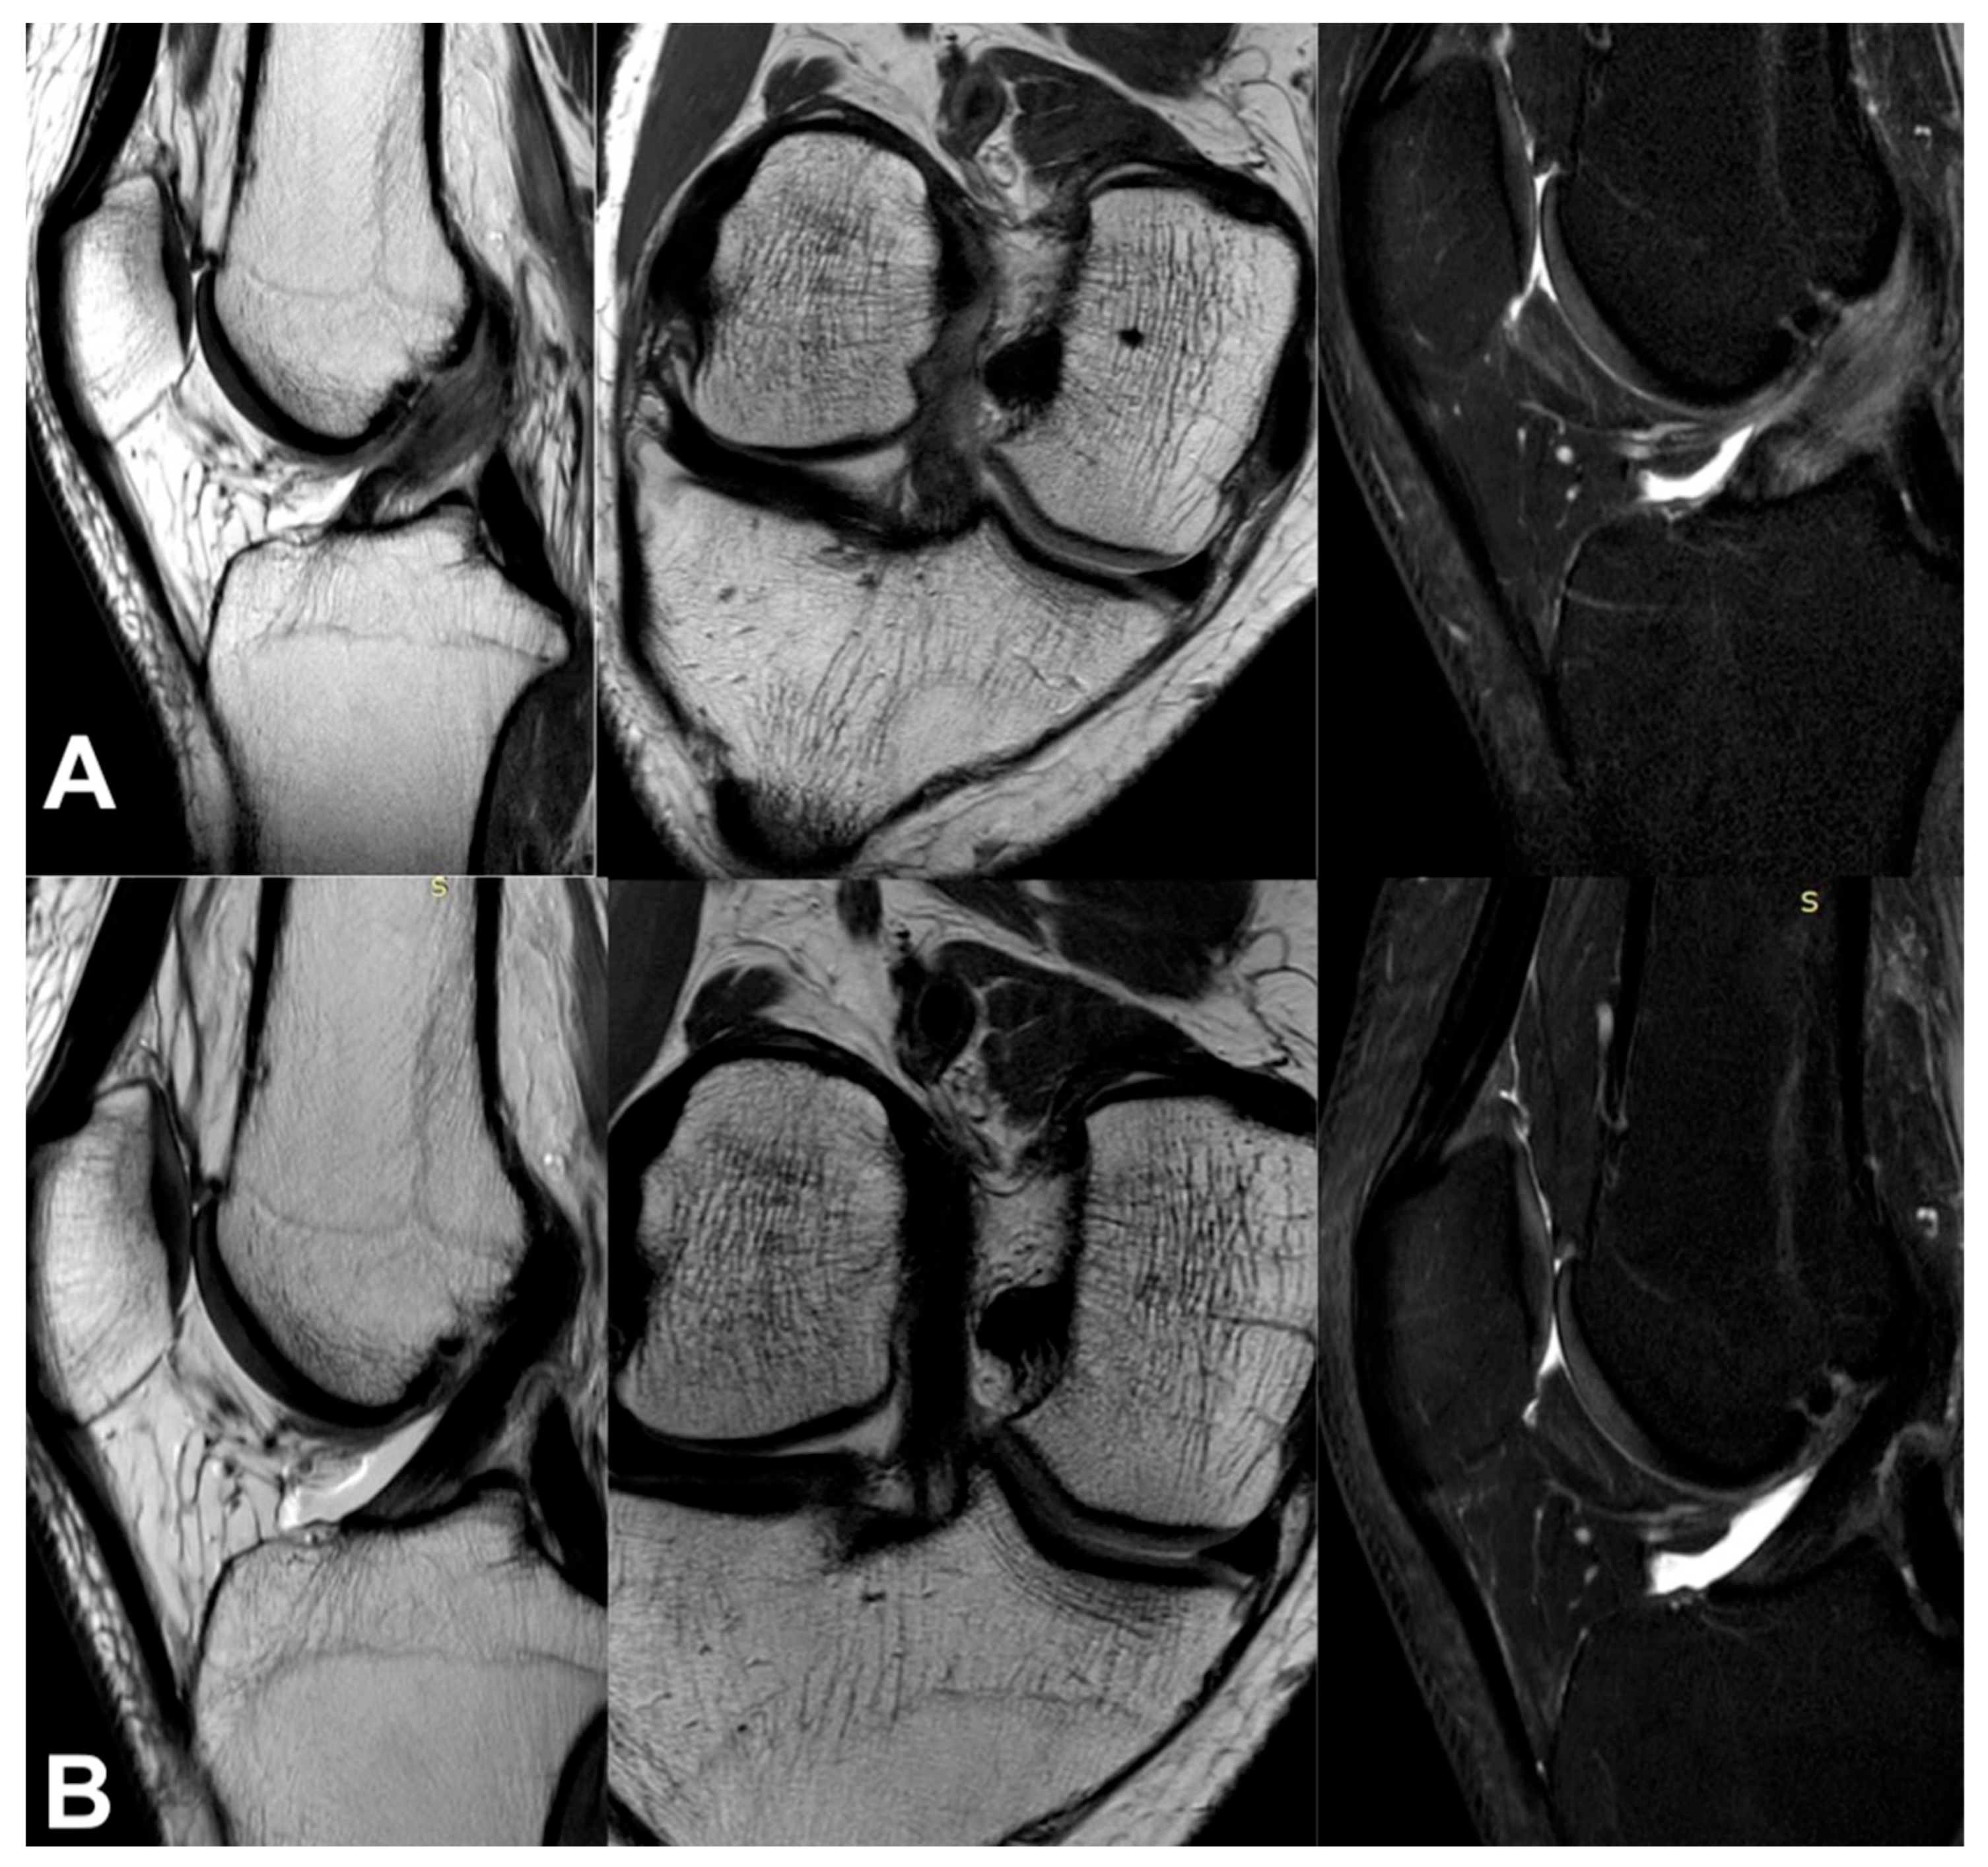

3.3. Imaging Analysis